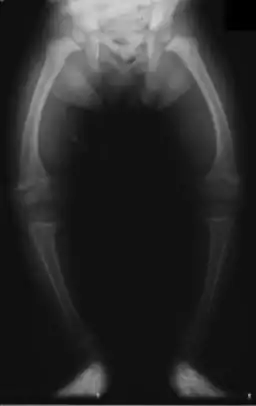

Radiografía de las piernas en un niño de 2 años de edad con raquitismo

Genu Varo es una deformidad frecuente de las rodillas en niños, secundaria a la posición intrauterina (también llamado piernas arqueadas y tibia vara), su forma fisiológica se corrige por lo general con el desarrollo normal del niño, sin embargo cuando este persiste más allá del segundo año puede ser patológico.[1] Es importante diferenciar el proceso fisiológico de la enfermedad de Blount (tibia vara), que es una peculiaridad física[2] marcada por una inclinación hacia afuera de la pierna en relación con el muslo, dando la apariencia de un arco. Por lo general, la angulación medial de ambos el fémur y la tibia está involucrada.